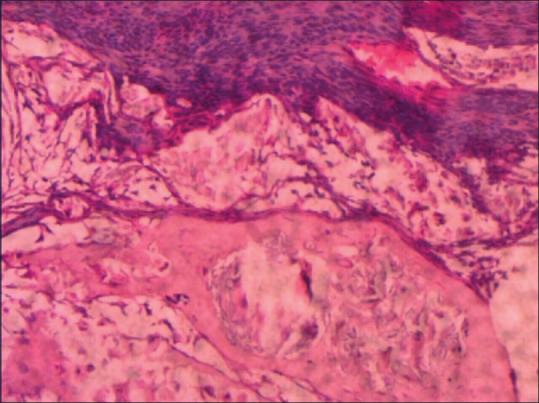

Osseous metaplasia (OM) of the cervix without involvement of the uterus is an extremely rare entity. Only few cases had been reported in the literature. We reported a rare case of OM of the cervix clinically mimicking cervical cancer. A 52-year-old female presented with chief complaints of leukorrhea and an unusual sensation of mass in the vagina. On clinical examination, the uterus, adnexa, pouch of Douglas, vulva, and perineum-all were normal except the cervix which was hypertrophied with surface irregularities. Histopathological examination of the cervix showed OM of the cervix. Since this is a benign entity, proper diagnosis is essential to avoid misdiagnosis of malignant tumors, especially malignant mesenchymal tumors.

Abstract Image